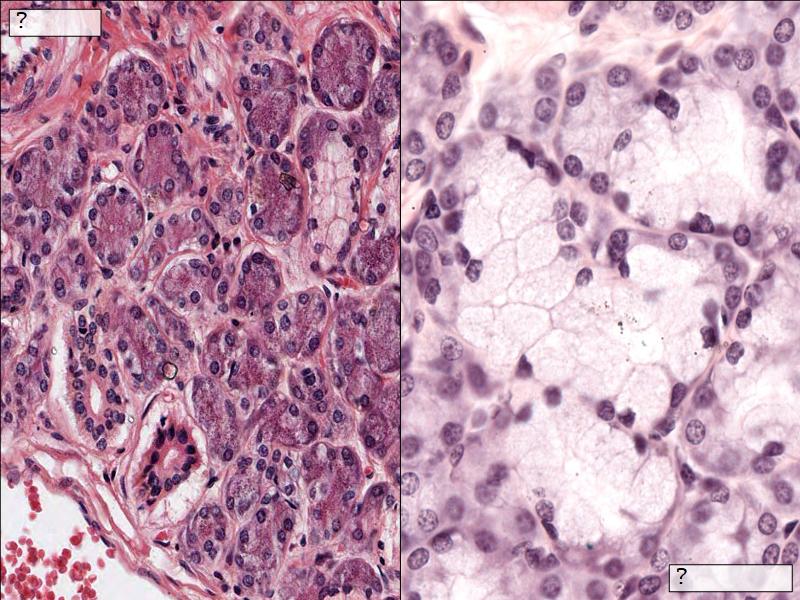

Cancer Association of South Africa (CANSA):Q03 - 1

List 2 types of exocrine secretions:

- Serous

- Mucinous

Mucinous and serous secretory units from the Virtual Microscopy Database at http://virtualmicroscopydatabase.org/

Title: Salivary Gland, Sublingual, Human

Title: Submandibular Gland

Owner: H Goldman

Drexel University - Collection Gastrointestinal System

Used under the BY-SA-NC Creative Commons License